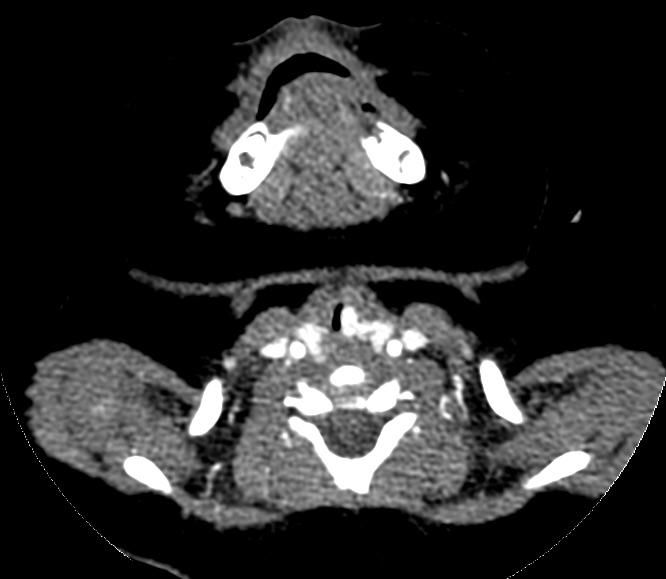

1.2诊断标准与方法对于可疑SGH患儿均需行纤维喉镜检查,声门下单侧或双侧局部隆起,表面光滑、暗红色,阻塞声门下气道,则高度怀疑SGH(图1)。颈部增强CT见声门下局部软组织增厚,气道变窄,增强扫描强化明显(图2a,b,c),诊断明确后给药。

颈部增强CT:左侧声门下局部软组织增厚,向气道内突起,强化明显。